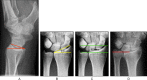

Diatal radius fractures (DRFs) are typical fractures of relatively fit persons with osteoporotic bone who remain active into older age. Traditionally, DRFs in older patients have been treated with closed reduction and cast immobilization. Considering the increasing life expectancy of the elderly population, appropriate management of these fractures is of growing importance. Decision making for surgical or nonsurgical approach to osteoporotic DRFs is difficult. These decisions are often made based on the data from treatments of much younger patients. The current literature concerning the treatment of DRFs in the elderly individuals is more controversial. Some investigators have recommended open reduction internal fixation (ORIF) as treatment for unstable DRFs in older patients, while others have suggested that elderly patients should be treated nonsurgically even if there is an unstable fracture situation because fracture reduction is not associated with functional outcomes as in younger patients. This article reviews the different treatment options for DRFs in the elderly individuals reported in the recent literature.